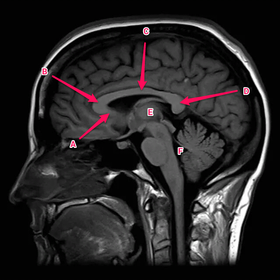

Anatomy practical midyear flashcard revision

anatomy

x-ray